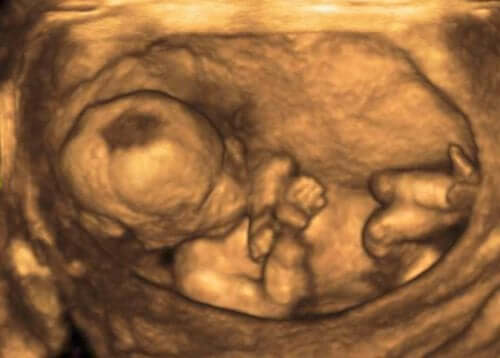

Medical professionals usually detect these alterations by an ultrasound procedure to measure the volume of amniotic fluid. They do so through the amniotic fluid index (AFI).

To get this information, the expert divides the uterus into four unobstructed quadrants, which they measure in centimeters. A normal AFI is between 3 to 8 inches (8 and 21 cm).